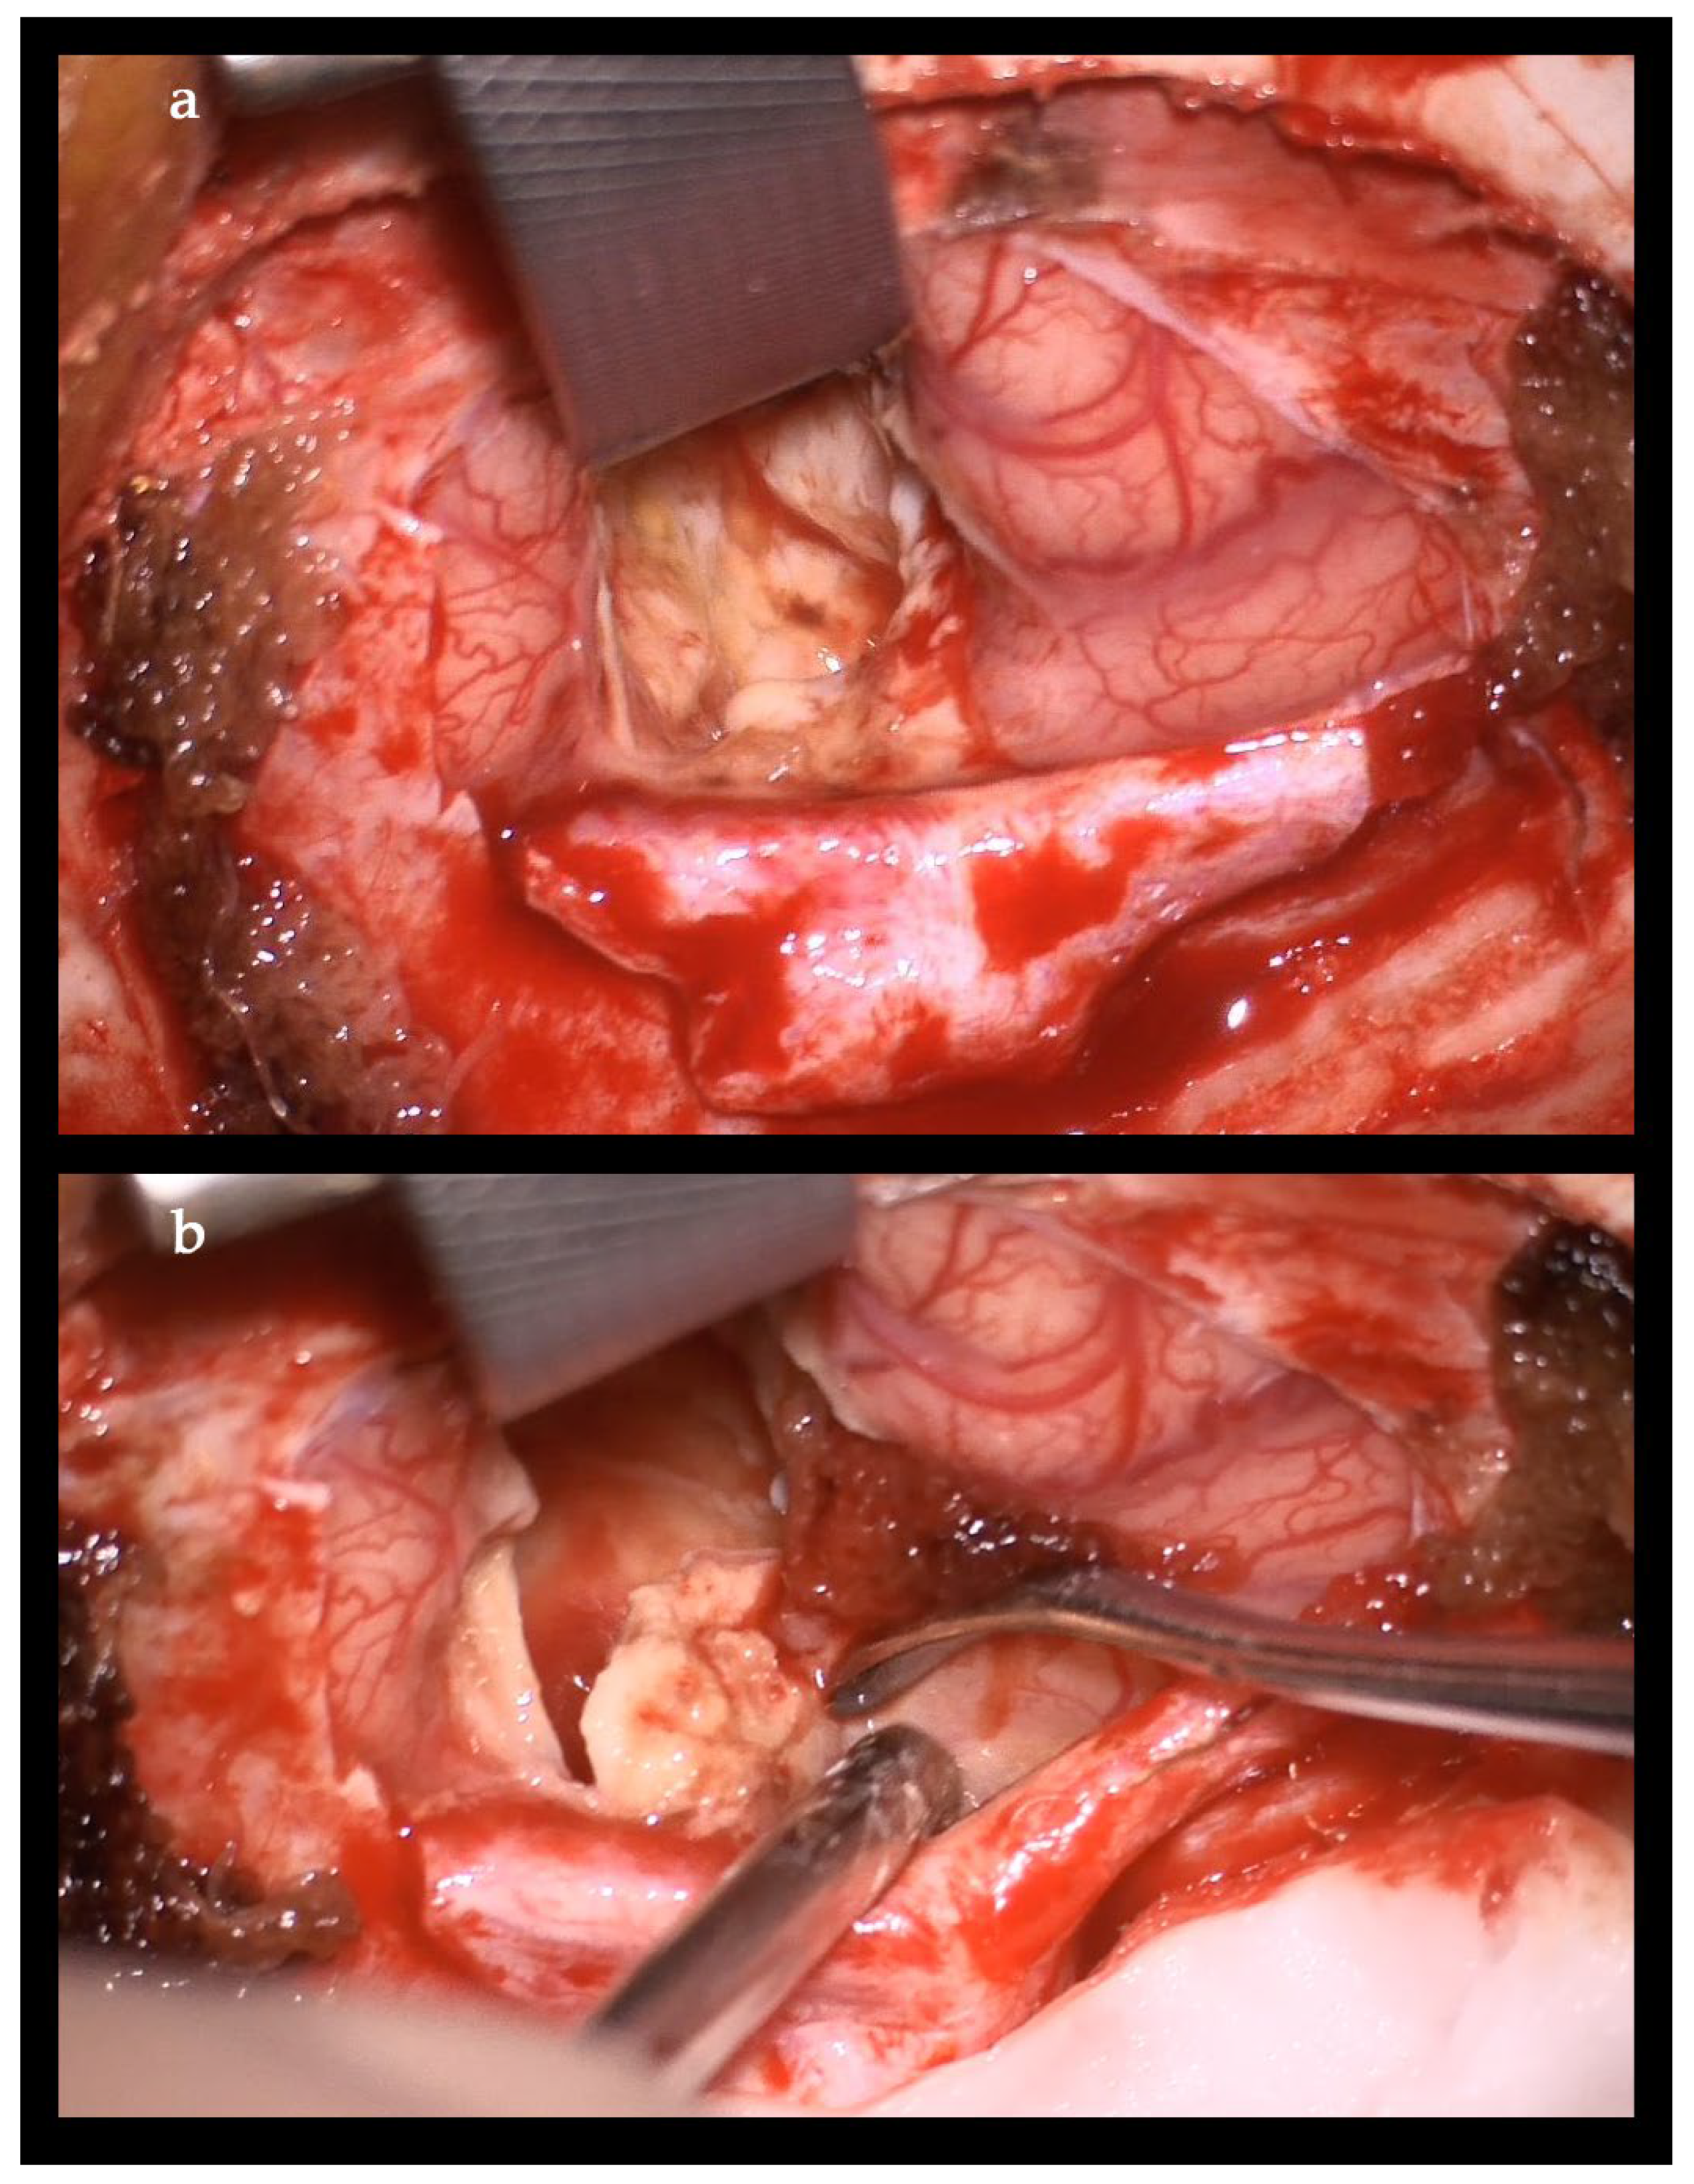

2. Case Report